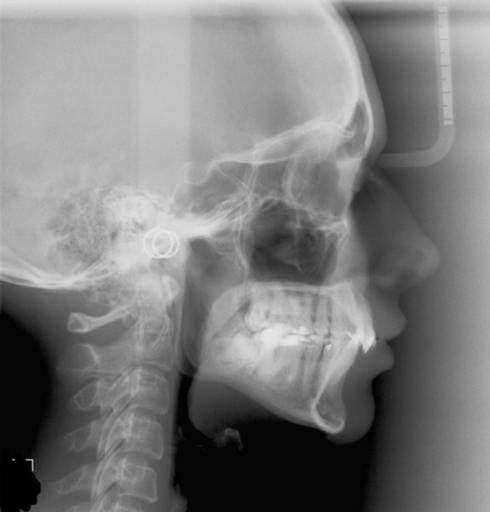

can I change orthodontist, in braces & everything is going wrong

I'm in desperate need of help. I'm currently in braces w/ an orthodontist & he says I will need jaw surgery eventually. He has expanded my teeth/bite even more & I can barely survive his treatment. I'm in a monster bite now (gigantic) and I presented w/ him a large bite and he made it longer even longer. I don't know what to do? Can barely speak, eat, move my head & he's making me worse. At this point I want my top teeth out just to get relief because this is going so very wrong. I think I'm over this orthodontist head & don't know what to do. Please advice. I'm a very chronic case so a lot of dentists won't touch me. Do you know of any where I can get my top teeth removed. Please help, I'm desperate. Thank you much. I'm also severely trapped under my maxilla (top teeth). This situation is very